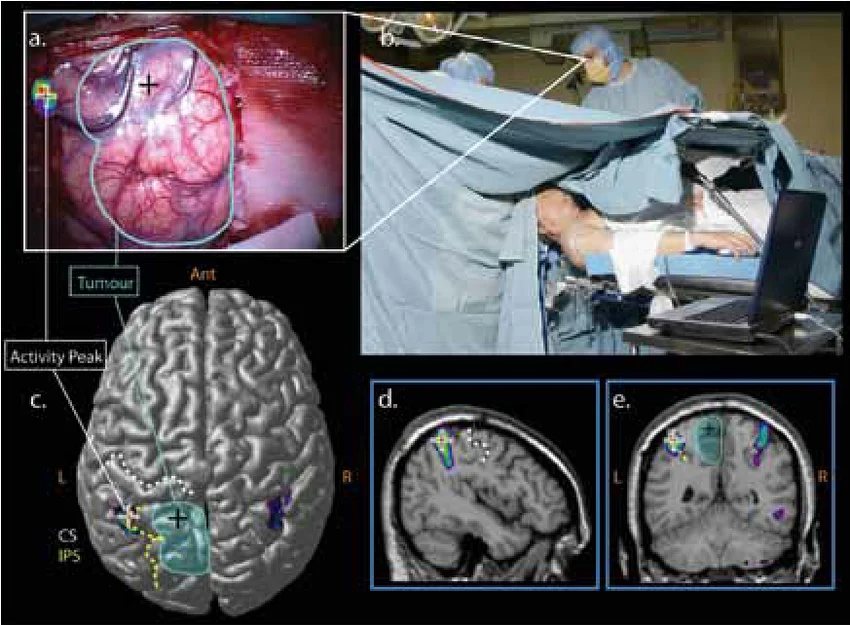

Neuronavigation-guided surgery

Neuronavigation-guided surgery uses advanced computer-assisted stereotactic technology to provide real-time, three-dimensional intraoperative navigation based on pre-operative imaging (MRI/CT), enabling precise localization of brain structures, tumors, and lesions during neurosurgical procedures. At The Brain and Spine Centre, Dr. Muhammad Aqeel Natt utilizes neuronavigation systems at Farooq Hospital, West Wood Branch, Lahore, to enhance accuracy, safety, and extent of resection in complex cranial and spinal surgery.​

Neuronavigation integrates preoperative imaging with intraoperative tracking to create a dynamic surgical map, similar to GPS for the brain; rigid registration aligns patient head to imaging dataset, and optical/infrared cameras track instruments in real-time. Systems compensate for brain shift (intraoperative deformation) using intraoperative imaging (iMRI/iUS) and augmented reality. Applications span cranial tumor resection, vascular malformations, epilepsy surgery, biopsies, DBS, and spinal instrumentation.